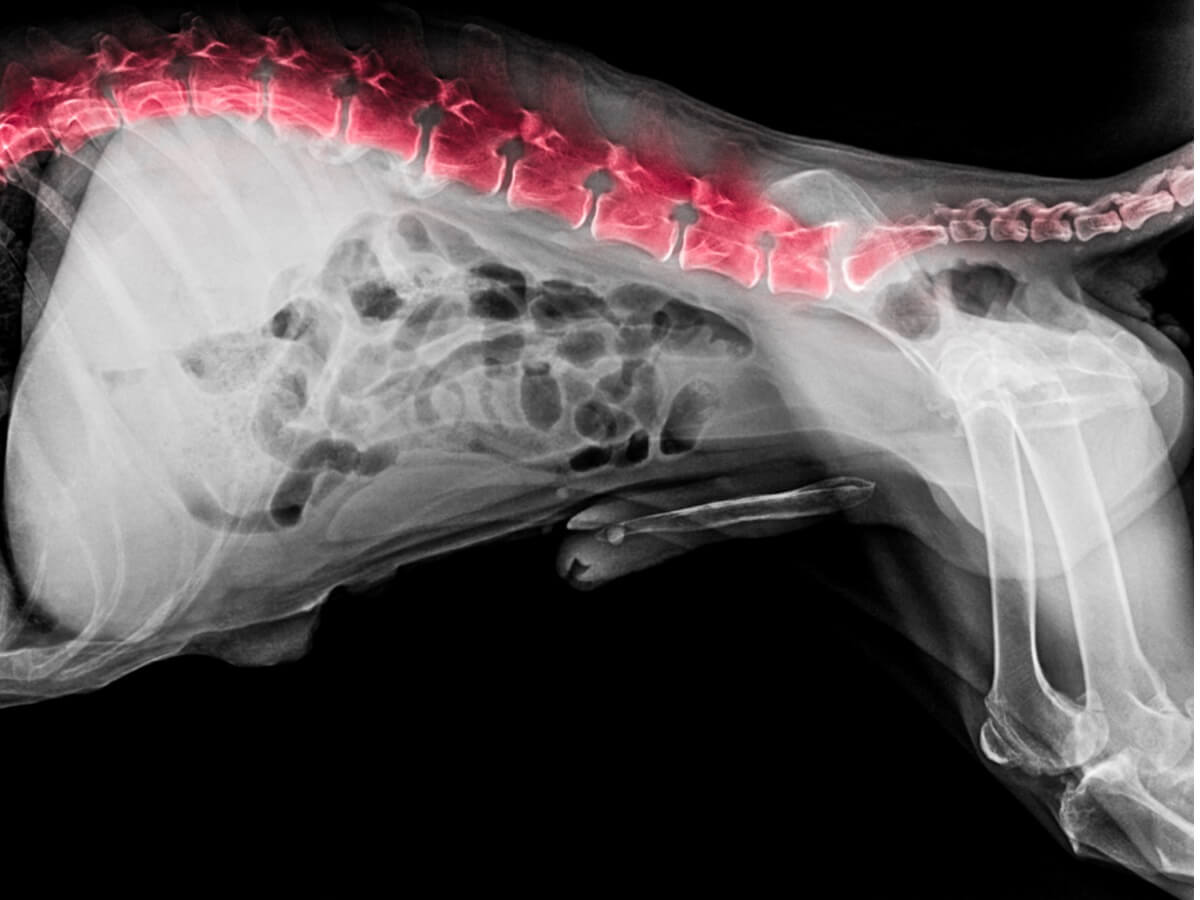

Buna ek olarak omurun durumunu gözlemlemek için radyolojik inceleme (röntgen ile) yapılır. Bu röntgen, ankilozan spondilit, herniasyon, intervertebral disklerin aşınması ve yıpranması, enfeksiyonlar, tümörler veya diğer rahatsızlıkların olup olmadığını belirleyecektir.

Sonuçlar hala net değilse, MRI veya BT (bilgisayarlı tomografi) ile ileri tanısal görüntüleme yapılacaktır. Bu teknikler yukarıda bahsedilen diğer yaklaşımlardan çok daha doğru ve kesin sonuçlar vermektedir.